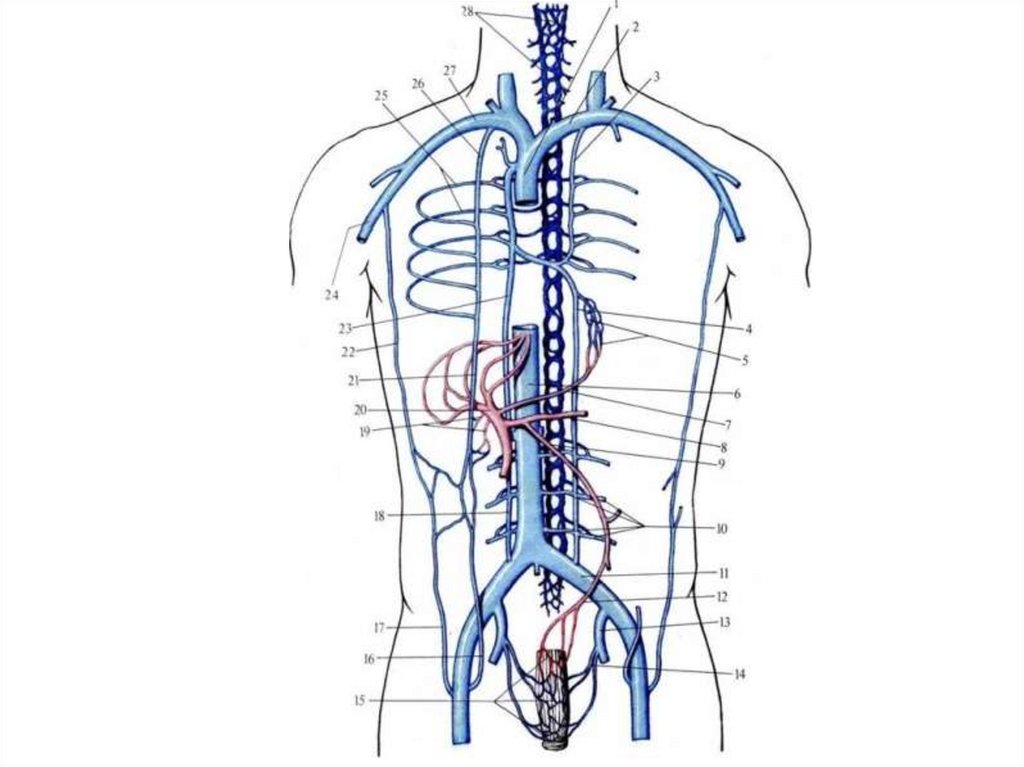

Схема системы верхней и нижней полых вен

Глубокие вены нижней конечности

Поверхностные вены нижней конечности

58. Схема системы верхней и нижней полых вен

1 — передняя яремная вена;

2 — наружная яремная вена;

3 — надлопаточная вена;

4 — внутренняя яремная вена;

5 — яремная венозная дуга;

6 — плечеголовная вена;

7 — подключичная вена;

8 — подмышечная вена;

9 — дуга аорты;

10 — верхняя полая вена;

11 — царская вена;

12 — левый желудочек;

13 — правый желудочек;

14 — головная вена руки;

15 — плечевая вена;

16 — задние межреберные вены;

17 — почечная вена;

18 — яичковые вены;

• 19 — правая восходящая поясничная

вена;

20 — поясничные вены;

21 — нижняя полая вена;

22 — срединная крестцовая вена;

23 — общая подвздошная вена;

24 — латеральная крестцовая вена;

25 — внутренняя подвздошная вена;

26 — наружная подвздошная вена;

27 — поверхностная надчревная вена;

28 — наружная половая вена;

29 — большая скрытая вена;

30 — бедренная вена;

31 — глубокая вена бедра;

32 — запирательная вена

59. Схема системы верхней и нижней полых вен

• 20 — поясничные вены;